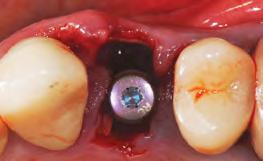

3. Image 3a: Tooth #9 was extracted with minimal flap elevation, preserving the papillae. Image 3b: A 3.6 x 15 mm implant was placed in a fully guided manner with a palatal bias to maximize the facial gap dimension, achieving a +2mm gap.

4. Image 4a: The underside of the periosteum was incised just apical to the mucogingival junction, and a supra-periosteal pocket was created using sharp dissection with a #15 blade. Image 4b: The facial gap was packed with 50 mg of Geistlich Bio-Oss Collagen®. A cover screw was temporarily placed to prevent bone graft granules from entering the implant chamber.